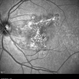

- macula serpiginous choroidopathy

- Tom Steele, CRA

TRC 50ex - Description

- 10/21/2009